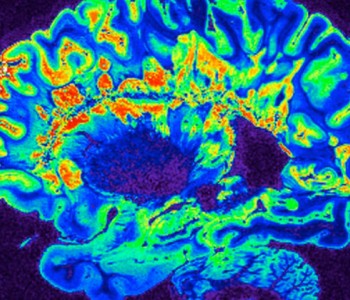

Индивидуальная стимуляция мозга поможет в борьбе с депрессией

Новое исследование продемонстрировало, как глубокая стимуляция может быть настроена на индивидуальную активность мозга для лечения депрессии, устойчивой к традиционным формам терапии.